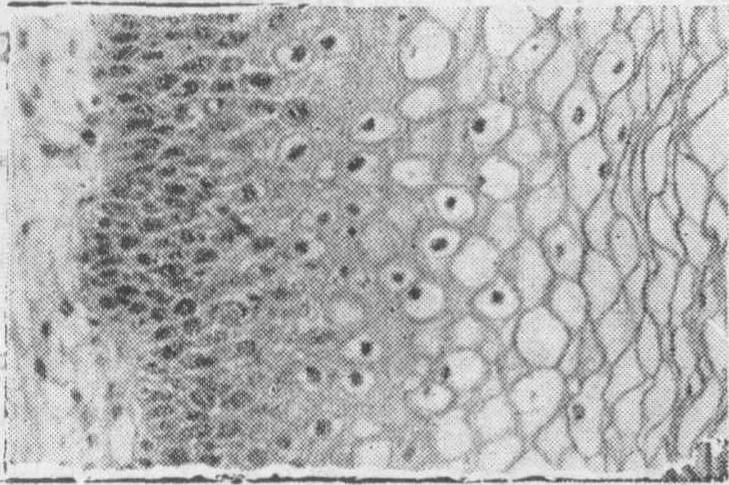

❸重度非典型增生(Ⅲ级)(图3)上皮的正常分化极度降低,细胞异型性明显,很接近分化型原位癌,但仍残留极少量的上皮正常分化,细胞的异型性不及原位癌明显,极性也未完全消失,并缺乏异常核分裂。

图3 宫颈重度非典型增生